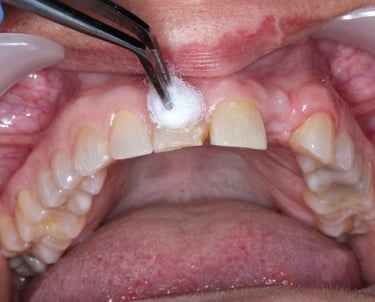

Es un procedimiento en el que se abre la cámara pulpar del diente para eliminar el tejido pulpar infectado o inflamado. Esto ayuda a aliviar el dolor y preparar el diente para un tratamiento de conducto.

Trepanación Pulpar (urgencia)